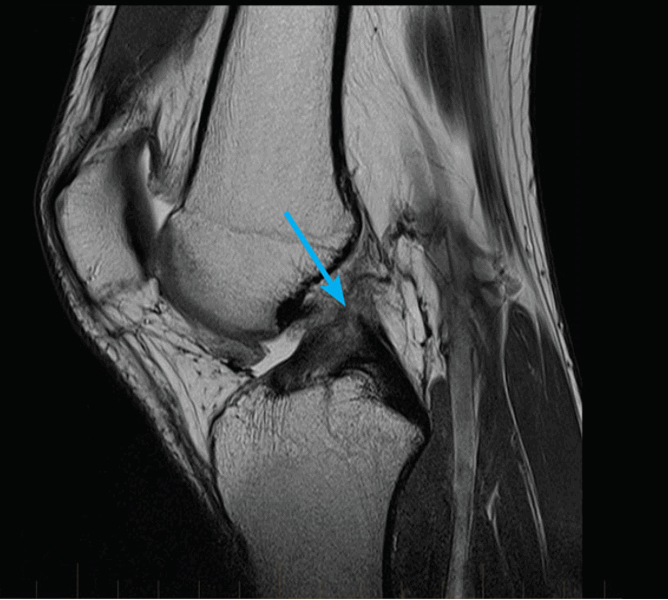

(Слева) МРТ Т2ВИ, сагиттальный срез: определяется небольшая околоменисковая киста с небольшими перегородками, возникшая после горизонтального разрыва переднего рога латерального мениска. Это типичная локализация формирования околоменисковых кист, но сопутствующий разрыв мениска в этой локализации не всегда визуализируется при МРТ или на операции.

(Справа) МРТ Т2ВИ, сагиттальный срез: у этого же пациента латеральнее визуализируется киста, детрит и перегородки Е внутри ее. Мениск был частично дис-коидным, а разрыв в некоторой степени сложным. (Слева) МРТ PDВИ, режим подавления сигнала от жира, аксиальный срез: у этого же пациента определяется распространение околоменисковой кисты, лежащей между средней линией сустава и соединением переднего рога и тела латерального мениска. Аксиальные изображения позволяют точно определить размер и распространение таких кист.